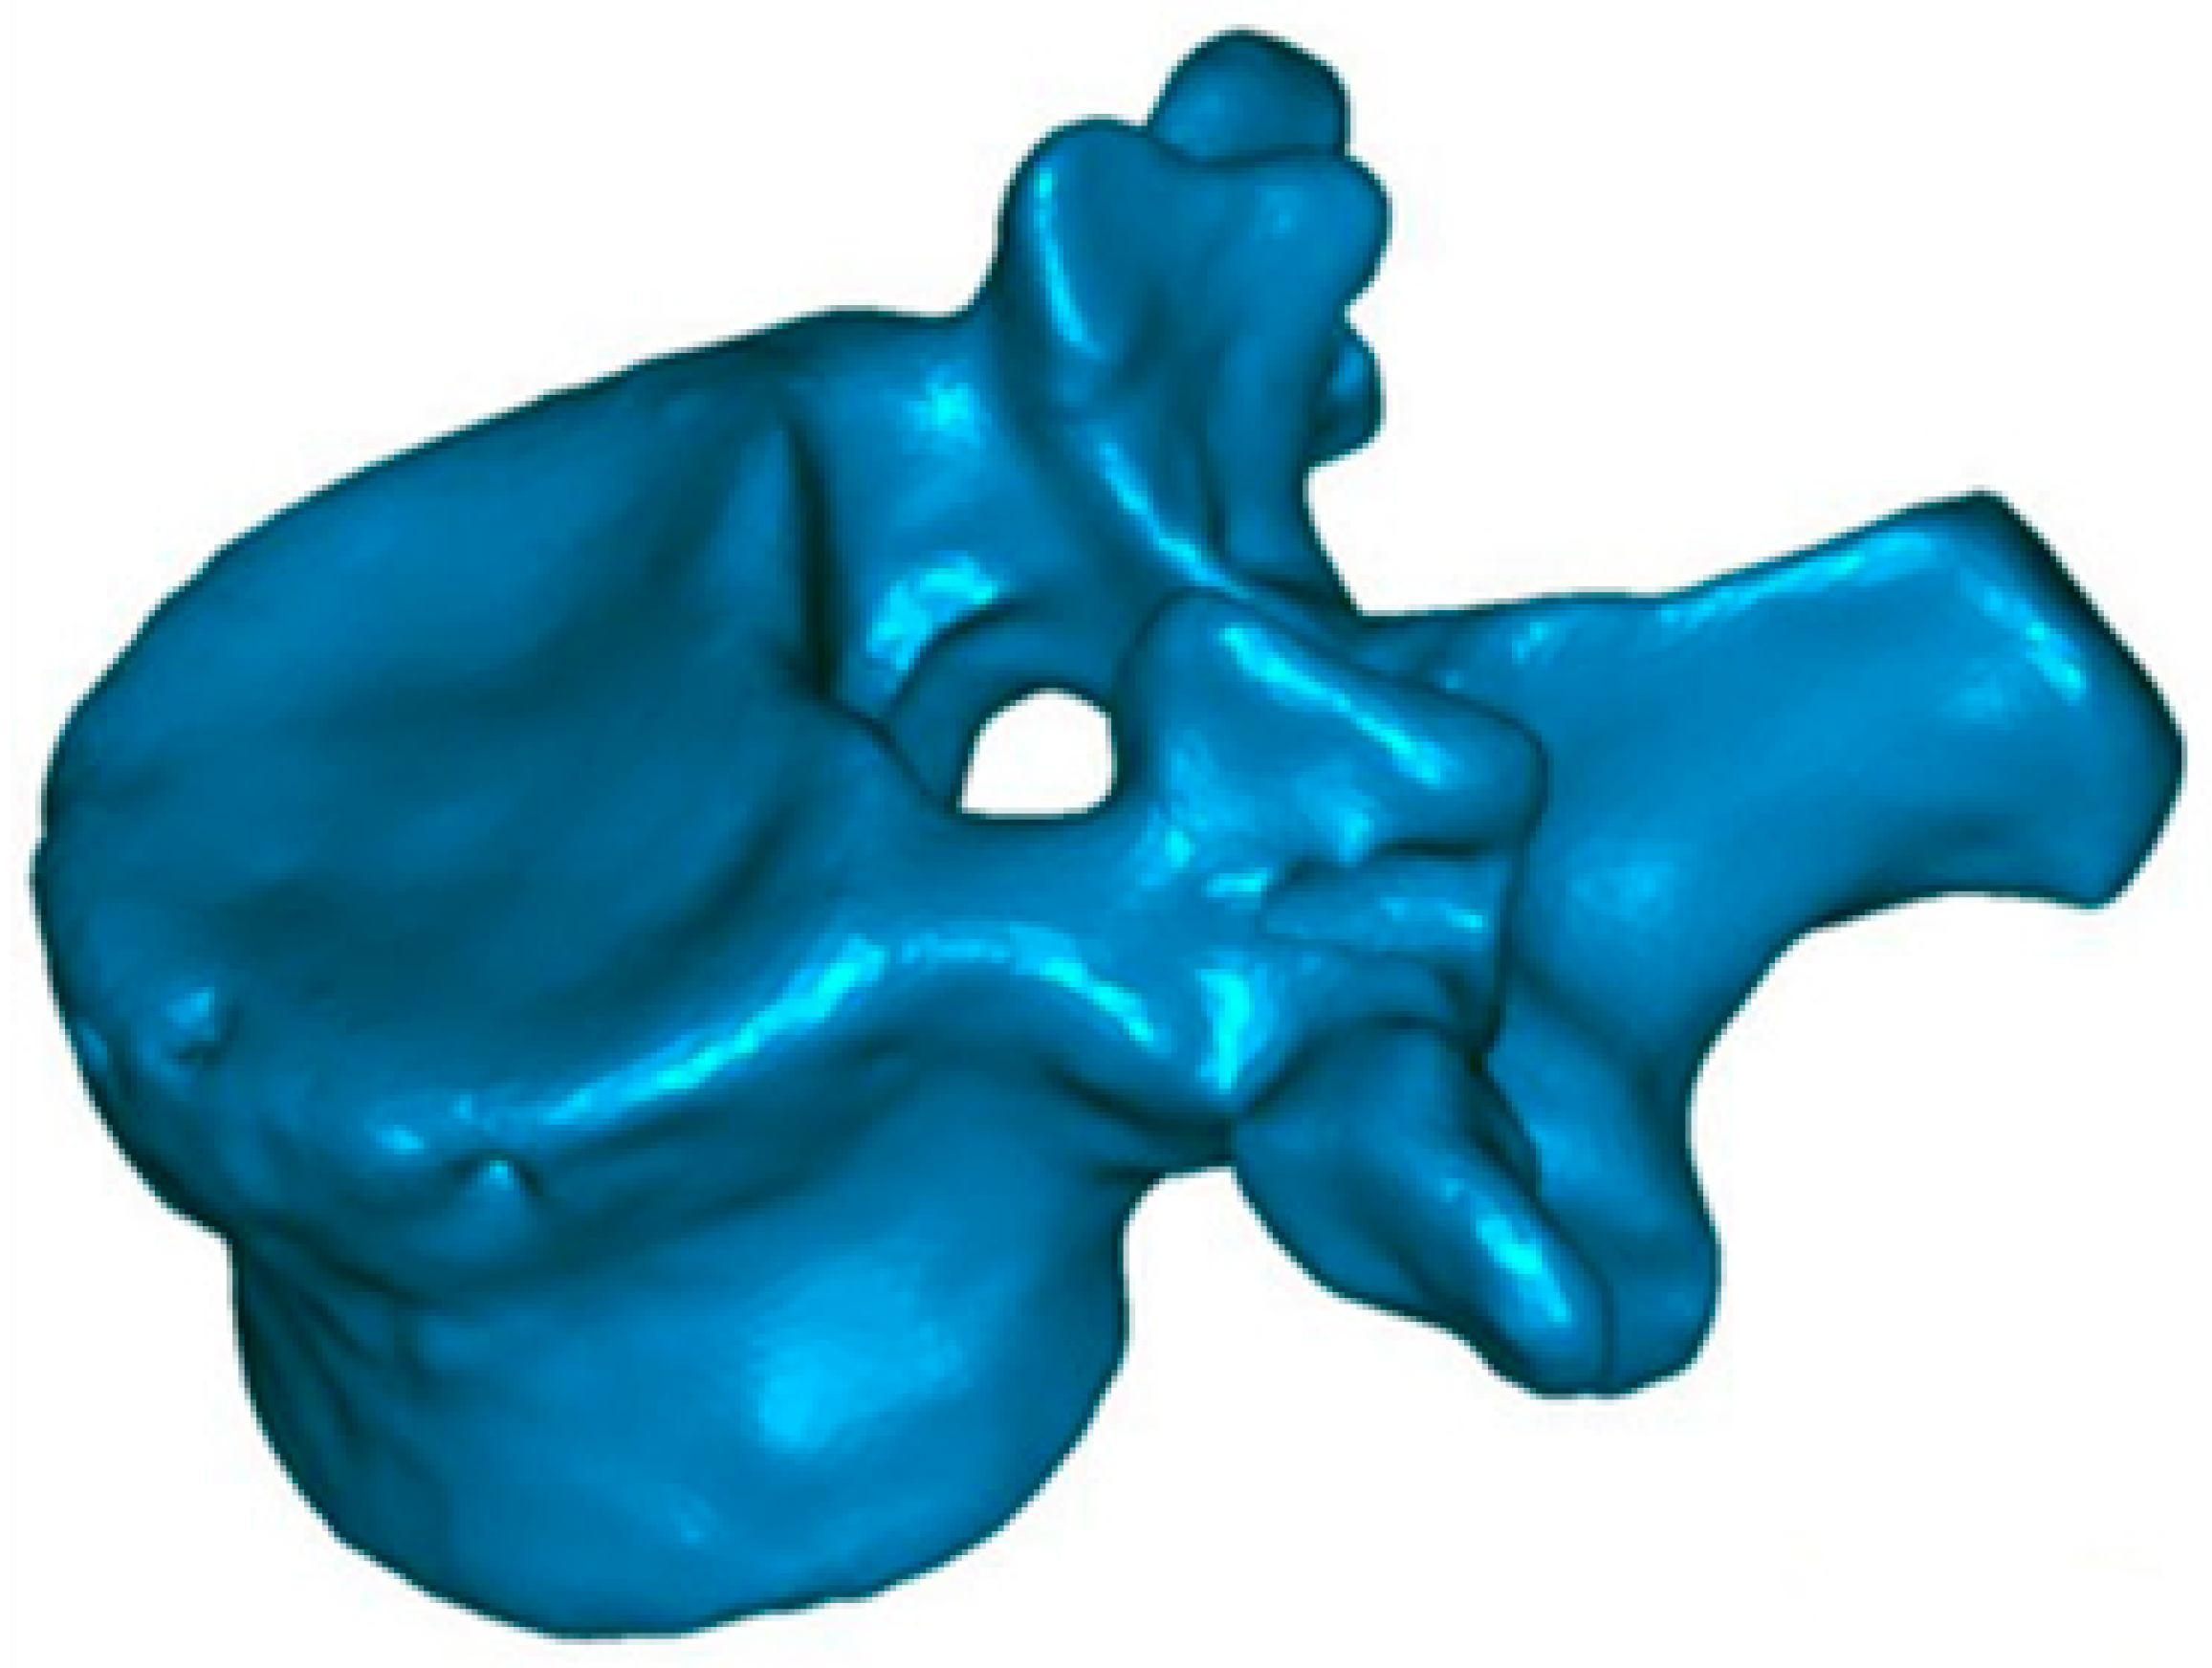

This method has been validated previously [38,39,40]. It permits comparing, in 3D, two vertebral reconstructions. Once the two 3D reconstructions were obtained for the same vertebra, before and after the intervention, they were superimposed (Figure 3). The posterior arch was affected by neither the VCF nor by the surgical procedure. The two 3D reconstructions are compared by calculation of the distance between the same point belonging to the vertebral body surface. These calculations can be presented by color-coded 3D mappings, in that the calculated distance is represented for any point with a specific colour depending on the measured value.

Figure 3.

Color-coded 3D mapping. Superimposition of the preoperative and postoperative reconstructions, obtaining the altitude line, corresponding to the “mm” of reduction of the different parts of the vertebra.

The precision of the measurements depends on the thickness of the tomography slices. In our application, each 3D reconstruction was obtained using millimetric slices, with a precision of ±1 mm. These 3D reconstructions also make possible to quantify the vertebral angular changes between the two endplates, without any bias. Therefore, based on the 3D reconstruction, the sagittal vertebral kyphosis angle was determined using the projection of the two vertebral endplates in the sagittal plane.